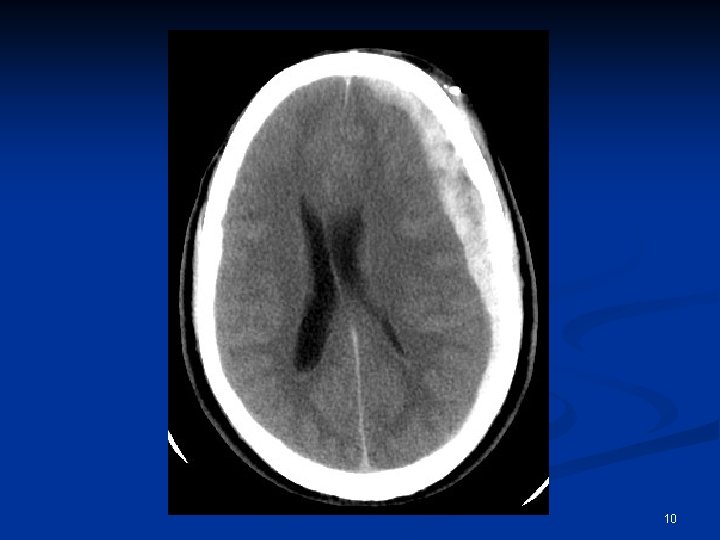

SDH n n n Blood collection between dura and arachnoid. Crescent shape Supratentorial Cross sutures, but not dural attachments May extend along falx and tentorium 11

Compressed lateral ventricle Obliterated CSF space Normal sulci Subdural hematoma 55